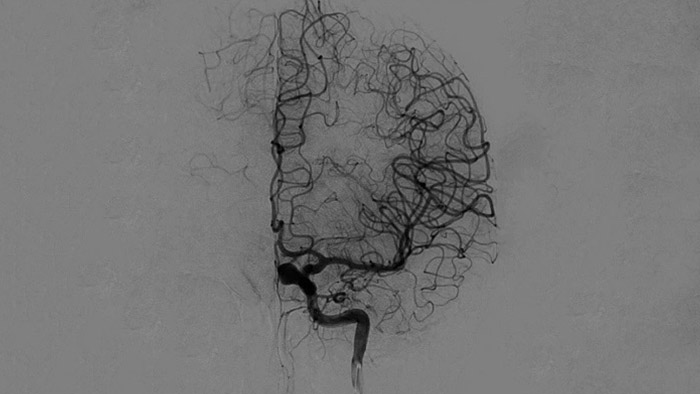

ClarityIQは、DSA撮影中の自動体動補正機能や、リアルタイム画像最適化処理により鮮明な画像を医師します。これにより、脳卒中治療において信頼性の高い画像での意思決定行うことができます。

高品質のDSA画像により、血栓が完全に回収されたかどうか、血栓の断片が脳内で遠位に分散しているかどうかを評価できます。また、ペナンブラへの血流の回復を確認し、治療前後の血流のチェックをすることができます。